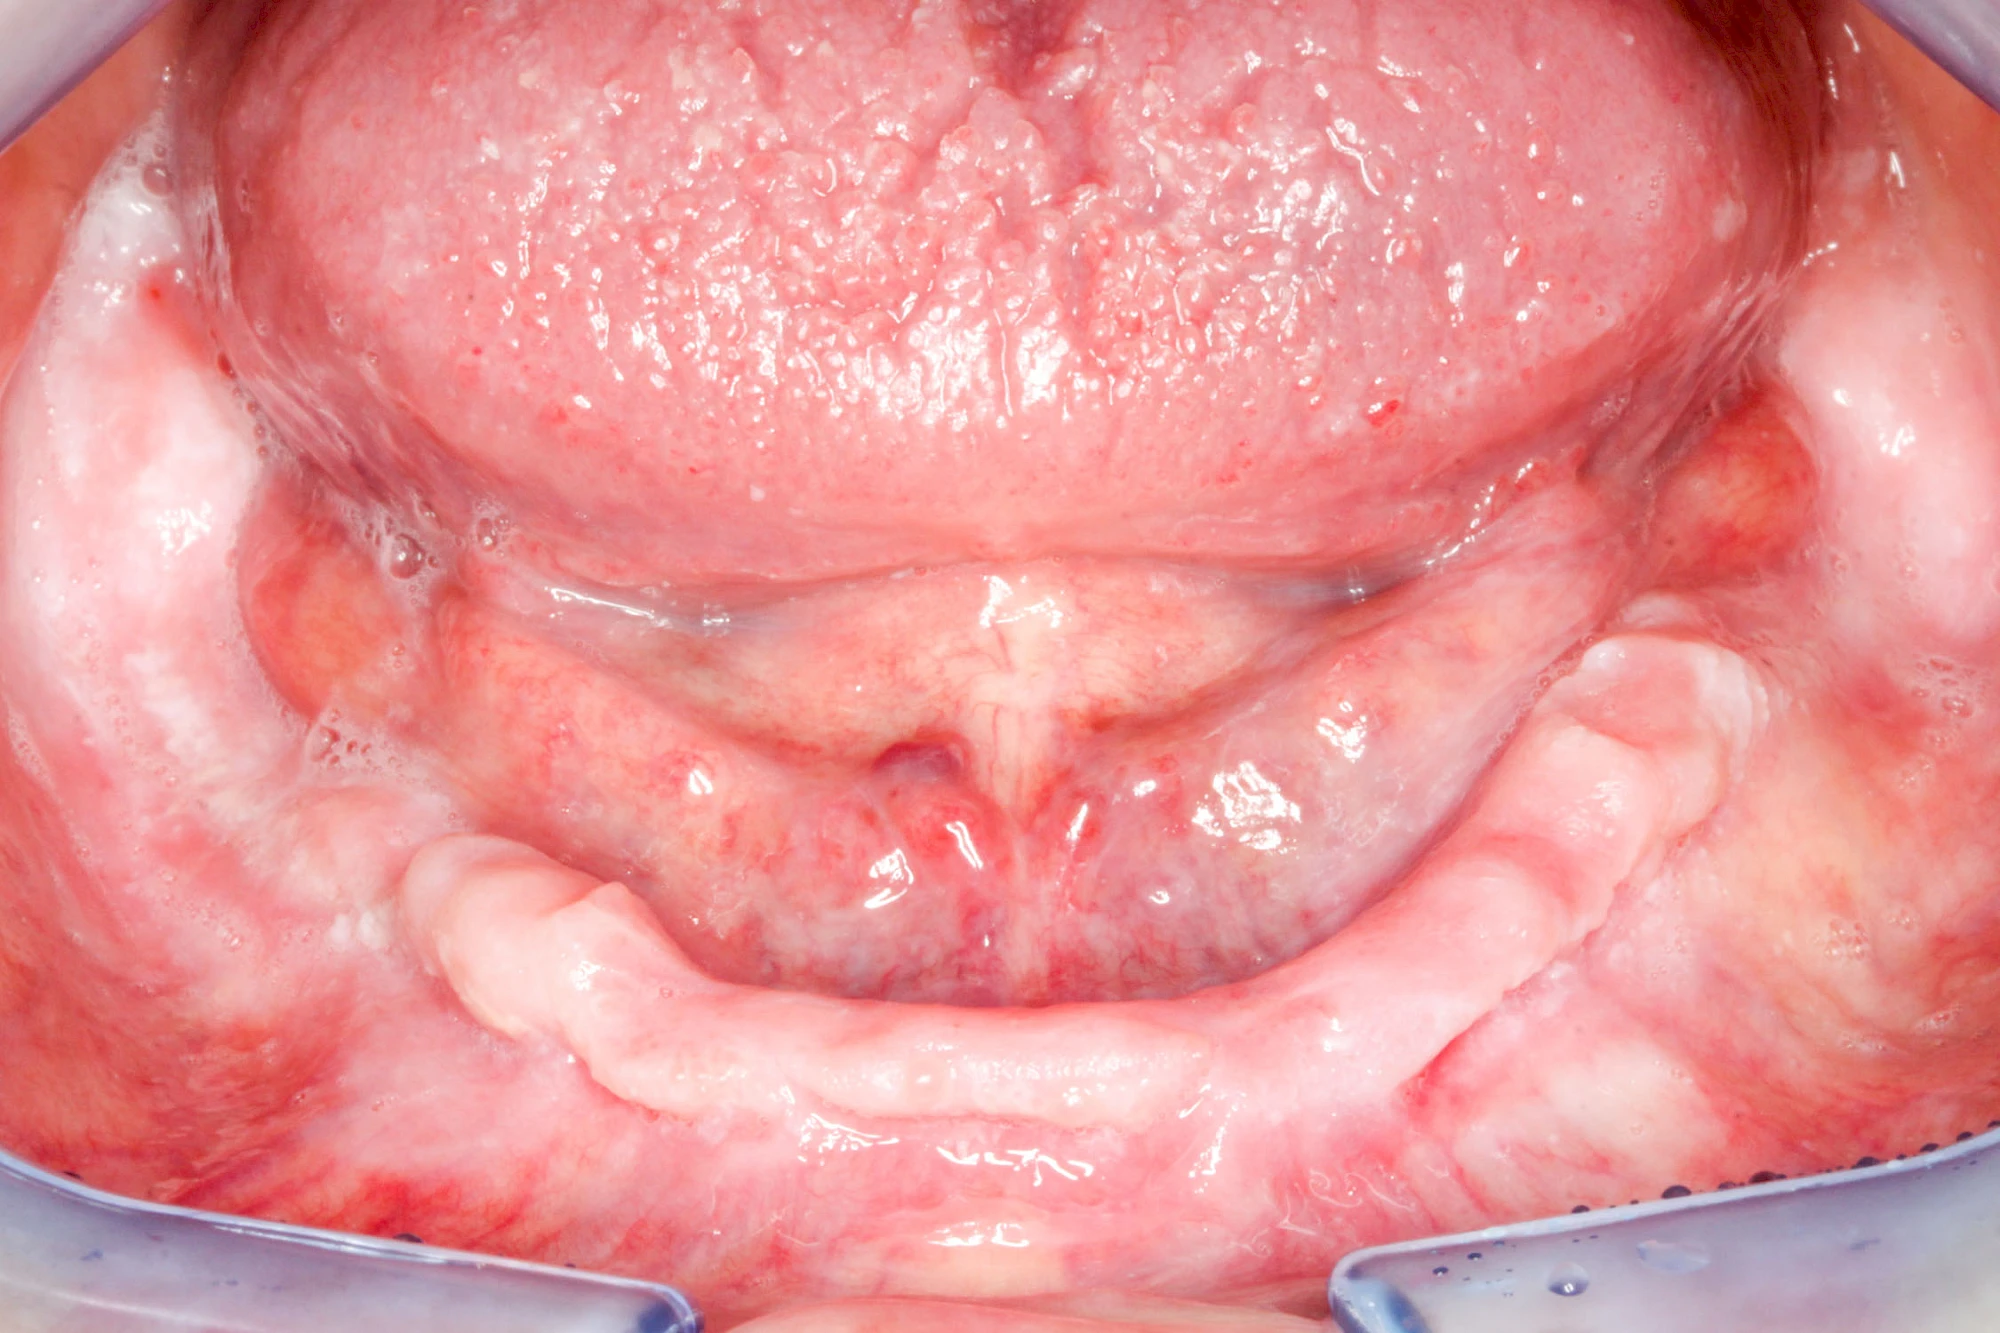

Überbein (Exostose)

Überbeine im Bereich der Kiefer sind gar nicht so selten. Häufiger im Bereich der Seitenzähne unterhalb des Zahnfleisches, aber auch in der Mitte vom Gaumen. Überbeine haben in dem Sinne keinen Krankheitswert, müssen also nicht operativ entfernt werden, wenn diese nicht stören. Überbeine können ein Anzeichen für Knirschen und Pressen sein.